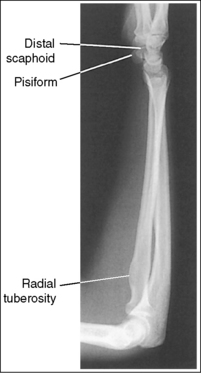

The distal forearm is in a lateral projection. The anterior aspects of the distal scaphoid and pisiform are aligned with each other, and the distal scaphoid is demonstrated slightly distal to the pisiform. The distal radius and ulna are superimposed.

• A lateral wrist and distal forearm projection is obtained by externally rotating the wrist into a lateral projection with its ulnar aspect against the IR (Figure 4-64). To ensure true lateral positioning, place the palmar aspect of your thumb and forefinger against the anterior and posterior aspects of the patient's wrist joint. Then adjust the rotation until your thumb and finger are aligned perpendicularly to the IR.

• Verifying a lateral forearm projection. The pisiform and distal scaphoid relationship can be used to discern whether a true lateral wrist and distal forearm are demonstrated. On a lateral forearm projection with accurate positioning, these two bones should be visible anterior to the capitate and lunate, with their anterior aspects aligned and the distal scaphoid projecting distally to the pisiform. It is the diverged x-ray beams used to image the pisiform and scaphoid that cause the distal scaphoid to be projected distally to the pisiform. When the wrist and distal forearm are rotated, the anterior alignment of the scaphoid and pisiform, as well as of the radius and ulna, changes. If the wrist and distal forearm have been externally rotated, the pisiform is visible anterior to the distal scaphoid, and the ulna appears anterior to the radius. The radial tuberosity will also be visible anteriorly if the elbow is placed in a true lateral projection (see Image 70). If the wrist and distal forearm have been internally rotated, the distal scaphoid is visible anterior to the pisiform and the radius appears anterior to the ulna (see Image 71).

The ulnar styloid is demonstrated in profile posteriorly.

• When the humerus and elbow are mispositioned, the placement of the ulna changes. The ulnar styloid is put in profile by placing the elbow in a lateral position and abducting the humerus until it is parallel with the IR, aligning the entire arm on the same horizontal plane. If the humerus is not abducted, nor the elbow positioned laterally, the ulnar styloid is positioned medially, out of profile.

The distal humerus is in a lateral projection. The distal humerus demonstrates three concentric (having the same center) arcs, formed by the trochlear sulcus, capitulum, and medial aspect of the trochlea. The elbow joint space is open, and the radial head is superimposed over the coronoid process.

• A lateral proximal forearm projection is obtained by placing the elbow in a lateral projection and abducting the humerus until it is parallel with the IR, thereby putting the entire arm on the same horizontal plane. The wrist and hand are then placed in a lateral projection, and the medial (ulnar) aspect of the forearm rests against the IR (see Figure 4-64). Even though the capitulum is placed anterior to the medial trochlea and the humeral epicondyles are not superimposed for this position, an open joint space may still be obtained. Because the central ray is centered to the midforearm, the diverged x-rays used to image the distal humerus align parallel with the slant of the capitulum and medial trochlea (see Figure 4-63). The result of this parallelism is an open elbow joint space.